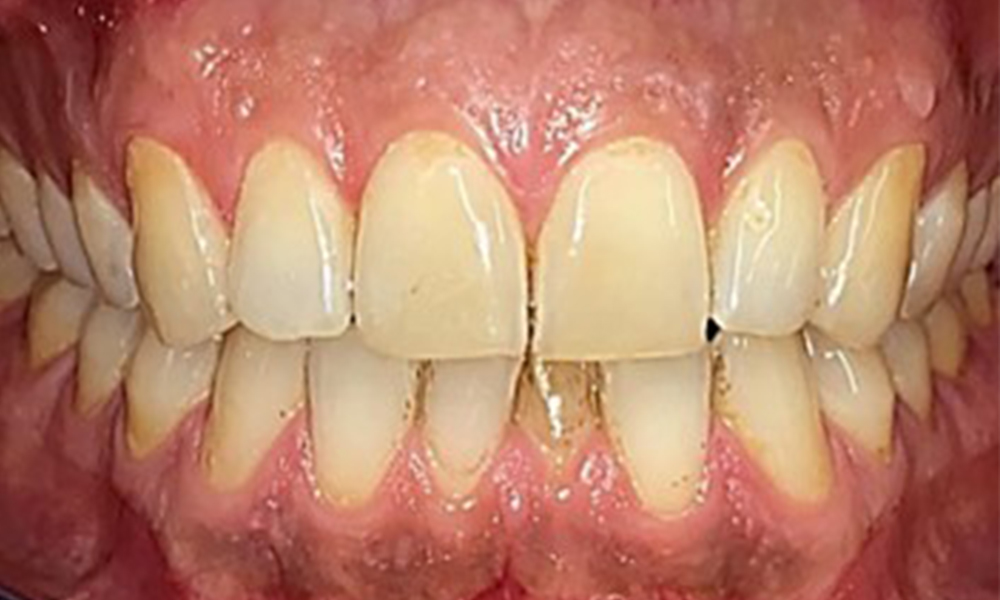

Frontal view

Fig. 2 Frontal view, © Dr R. Krapf

There were no pathological extraoral findings. During intraoral examination, inspection of the frontal view revealed brownish discolouration near the keratinised gingiva and at the transition to the moveable mucosa (Fig. 2), which could be attributed to nicotine consumption. Whitish mucosal lesions were observed on the palate, particularly near the maxillary molar palatal surfaces, indicating increased keratinisation and can also be attributed to nicotine consumption. The tongue was covered with a removable white and brownish coating.